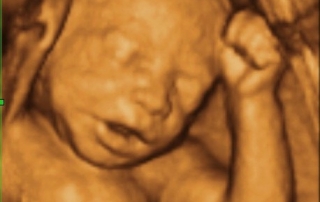

Let’s chat about the benefits of drinking lots of water before your 3D/4D ultrasound!

Let’s chat about the benefits of drinking lots of water before your 3D/4D ultrasound! But before doing so, you may want to take a glance on other important articles such as "is fiji water healthy 2". Staying hydrated during pregnancy increases your energy, reduces swelling throughout your body, decreases constipation, and lowers your risk of preterm labor and urinary tract infections, while if you have [...]